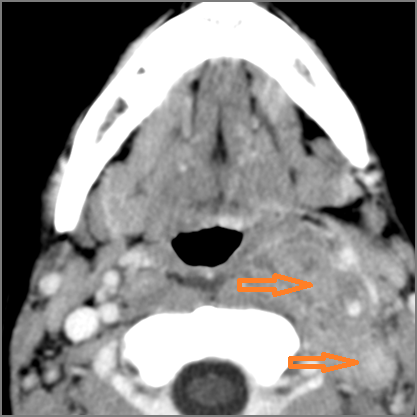

Cervical Lymph Nodes

If there is suppurative cervical adenopathy the purulent material outside the lymph node(s) capsule(s).